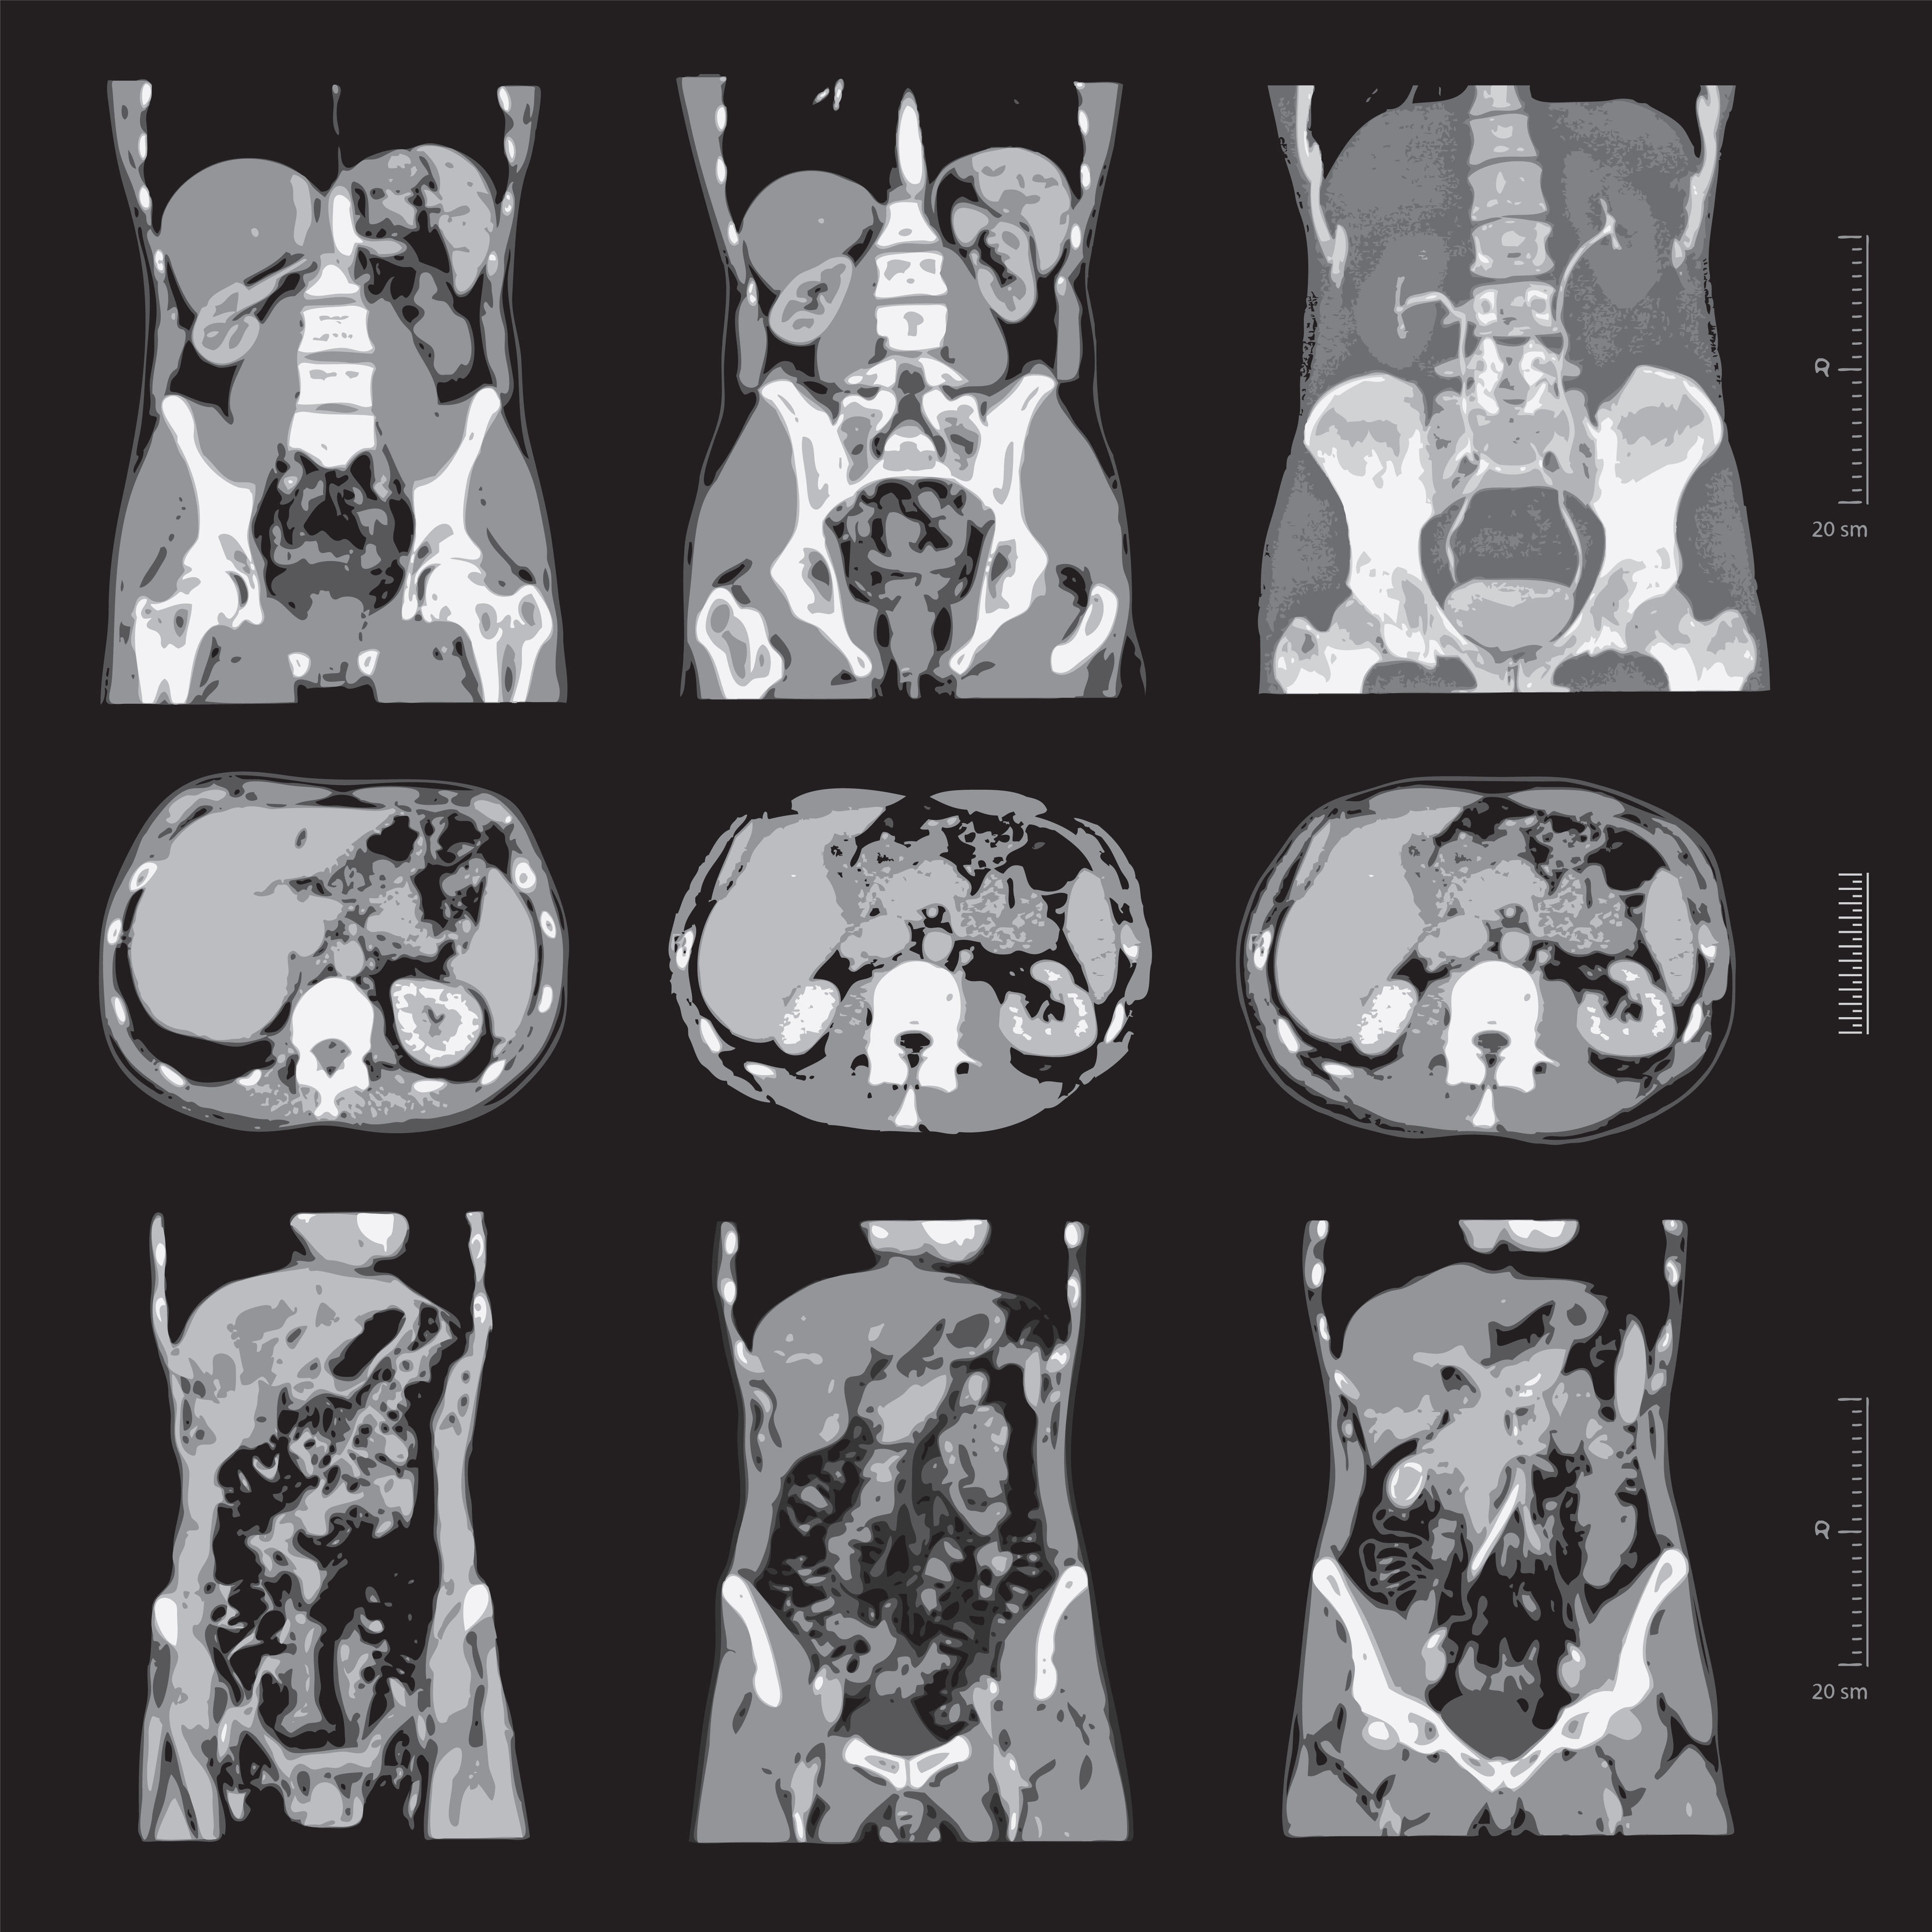

Le diagnostic est fait lors d’une biopsie ou d’une conisation. Une fois le cancer du col de l’utérus diagnostiqué, le bilan d’extension pour déterminer l’étendue de la maladie peut comprendre : une IRM pelvienne, un scanner ou un PET scanner. Des tests sanguins peuvent également être effectués pour évaluer la présence de marqueurs tumoraux qui pourraient indiquer la présence de cancer ailleurs dans le corps.